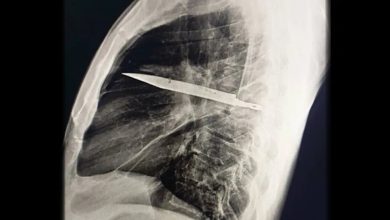

به گزارش آفتابنگاران، در یکی از نادرترین موارد پزشکی ثبتشده، مردی ۴۴ ساله اهل تانزانیا با ترشح چرک از قفسه…